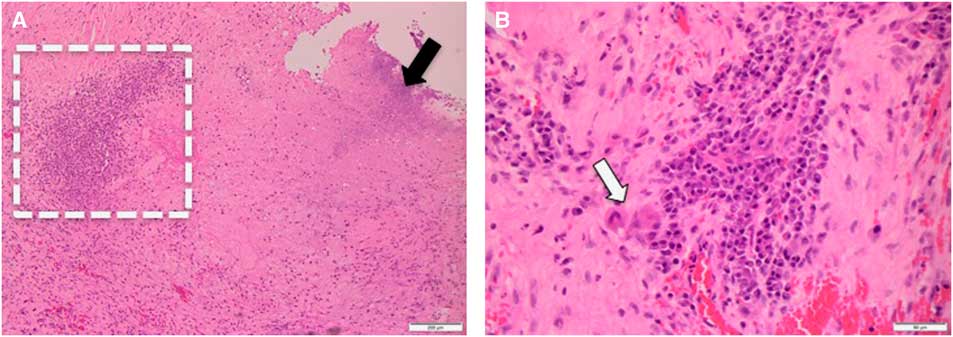

Neuropathology investigation revealed mixed inflammatory infiltrates in a dense collagenous tissue (Figure 2). The infiltrate was composed of lymphocytes, histiocytes, neutrophils, and plasma cells. Multiple necrotic foci were noted, which were likely associated with previous Gamma Knife treatment. No microorganisms were demonstrated on both hematoxylin and eosin stain, as well as special stains for bacterial (Gram stain), fungal (Grocott’s methenamine silver stain), or mycobacterial (Ziehl-Neelsen stain). Based on the absence of microorganisms, it is reasonable to conclude that granulomatous inflammation was associated with the Teflon implant.

Figure 2 Panel A: Medium power view (at 100×) shows necrosis (black arrow) and inflammatory infiltrate (dashed rectangle). Panel B: High power view (at 400×) of the inflammatory infiltrate. Note presence of multinucleated giant cells (white arrow).